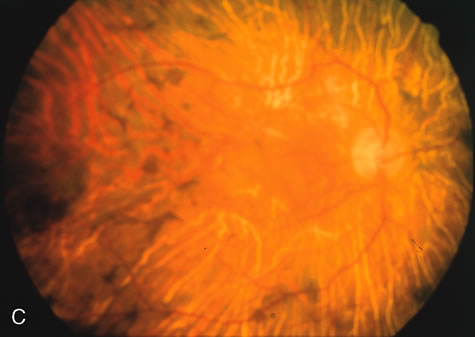

Generalized choroidal dystrophy is usually noted in middle-aged mildly symptomatic individuals who show a predominantly peripapillary or pericentral distribution of choroidal atrophy. Gradually, over the years these areas enlarge to eventually involve the entire retina. These changes are vividly seen on FA (Fig. 6).

Fig. 6. Generalized choroidal dystrophy. This 65-year-old woman gradually developed enlarging, progressive areas of choroidal atrophy over a 20-year period. When initially seen, the abnormalities were confined to the peripapillary and macular region (A,B). In a recent examination, the generalized choroidal atrophy is vividly demonstrated on angiography (C–F).